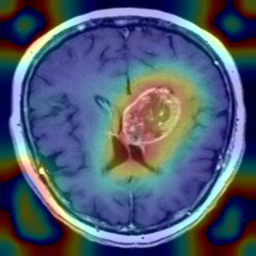

Figure 1: Heatmap Comparison of Unhealthy Images. Different columns show unhealthy MRI images of different positions, sizes, and textures. The first row is the raw image. The second row is the heatmap predicted with PatchCore. The third raw is the heatmap predicted with the proposed method.